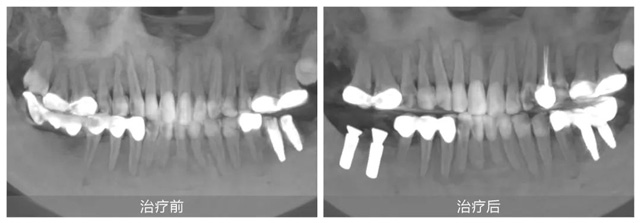

她自小牙齒不好,早年正牙過程中不幸遭遇正畸片切不當導致下頜右側兩顆磨牙嚴重受損,之后未經正規處理直接拔牙,造成重要磨牙缺失,嚴重影響咀嚼功能。隨后原治療機構采用傾斜智齒制作了不良烤瓷長橋修復,導致前磨牙牙髓壞死造成根尖炎。雪上加霜的是,五年前又被某口腔機構蹩腳醫生把上頜兩側磨牙做了不必要的牙冠,之后下頜左側兩顆磨牙也因種植體位置不正導致牙冠頻繁脫落,種植體也有折斷風險。

果然,徐會醫生不負所托輕松完成了劉女士下頜左側的牙冠修復。并對其他牙齒問題提出了一套綜合治療方案:先拆除不良修復體,拔除下頜右側的傾斜智齒,然后在缺牙處植入兩顆種植牙,并對前磨牙實施根管治療。這一方案更加微創,也更加經濟和高效。

在種植手術順利完成后,劉女士多次到院指定由徐會醫生負責后續下頜三顆牙齒的治療:“每一次治療結束,我都感覺離口腔健康更近了一步。感謝新橋口腔,感謝徐醫生,讓我看到了希望!”